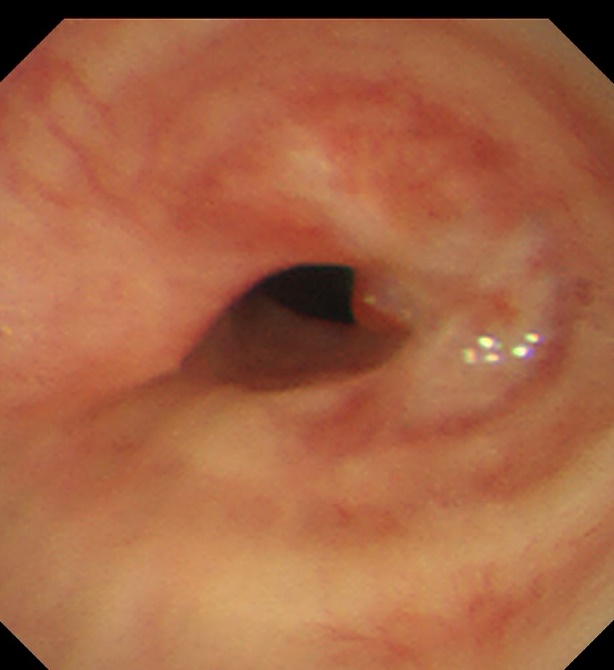

气管下段狭窄治疗前

患者,女,50岁,因“外伤后呼吸困难2月”来到华人色情 全科医学科治疗。患者2月前因外伤致气管撕裂,在当地医院行气管修补术,术后出现进行性加重呼吸困难。患者来到我院住院后,稍微活动就会感到气促,已不能活动,肺功能显示重度阻塞性肺通气功能障碍,胸部CT显示气管下段重度狭窄,支气管镜检查显示气管下段距隆突2cm处重度瘢痕狭窄,最窄处仅4mm,随时都会发生窒息甚至猝死,手术迫在眉睫!